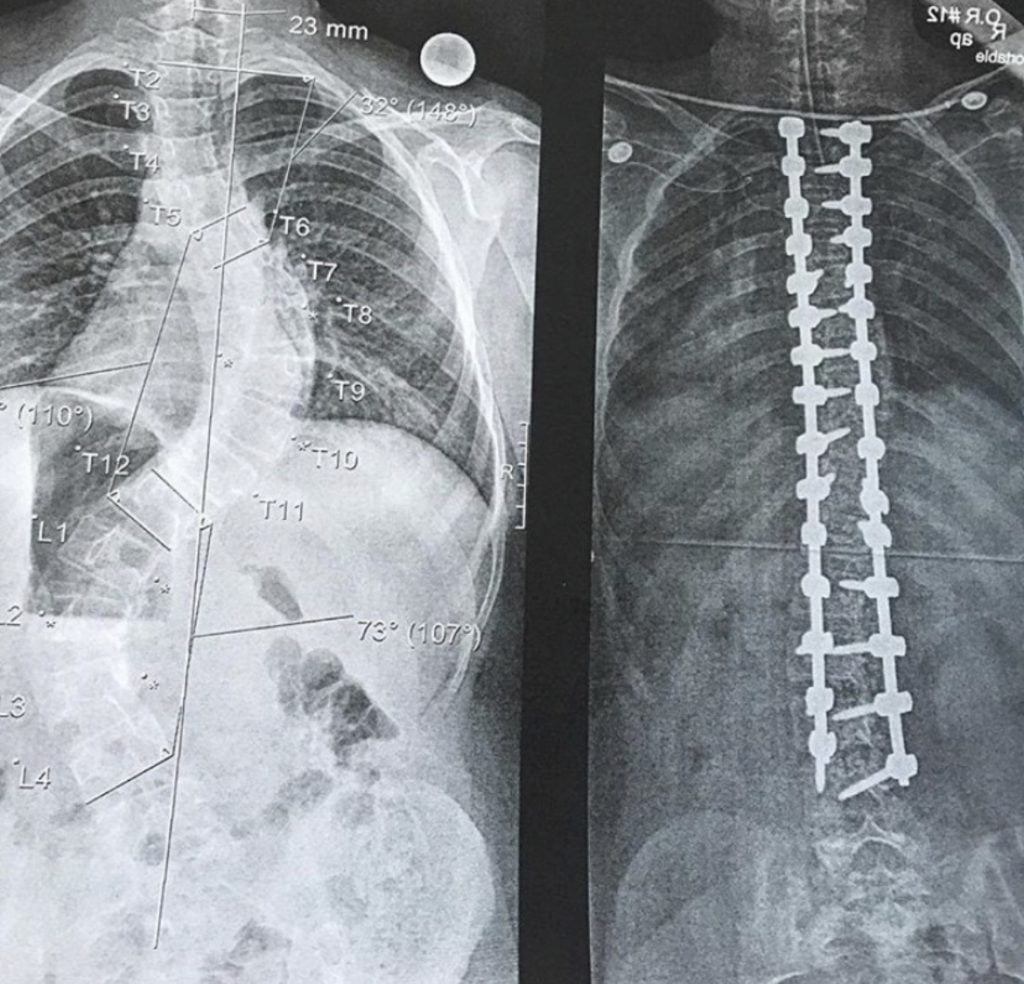

At 15-years-old, they told me my spine was pressing on my heart and my lungs. I needed to have surgery ASAP! I met with a few different surgeons and immediately knew Dr. Widmann was the one for me. The recovery was rough for a little bit but really not as bad as you think it’s going to be! Today is 7 years later and I sometimes forget I ever had surgery! I am fully functional and healthy!